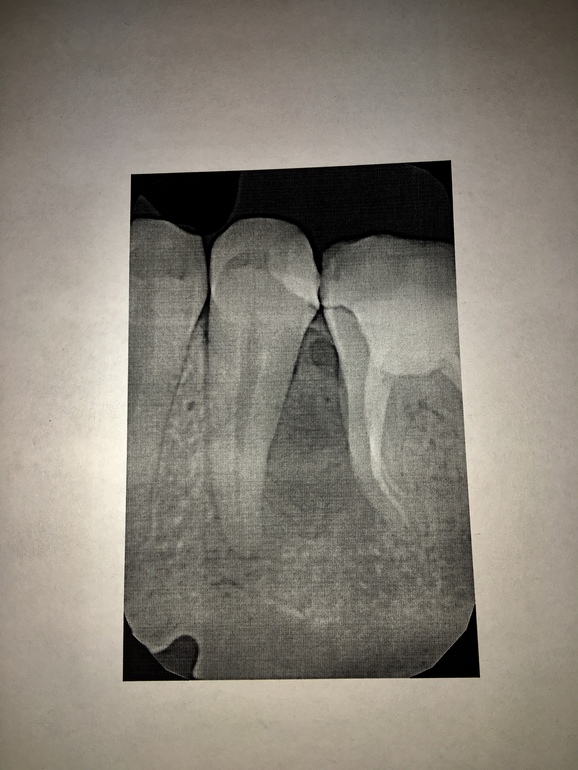

Киста в десне (рентген внизу)

СтоматологияДва месяца назад распухла десна снизу 5(живого) и 6(мертвого) зуба.

На рентгене воспаление. Врачи сказали, что образовалась киста в кости.

Стоматолог говорит, что надо вскрывать пятый зуб и чистить каналы. Если не поможет, хирург удалит его, и через отверстие от зуба удалит эту кисту.

P.S. В итоге мне сделали операцию. Вскрыли десну и кость сбоку, кисту удалили. Зубы оставили. Операция тяжелая достаточно